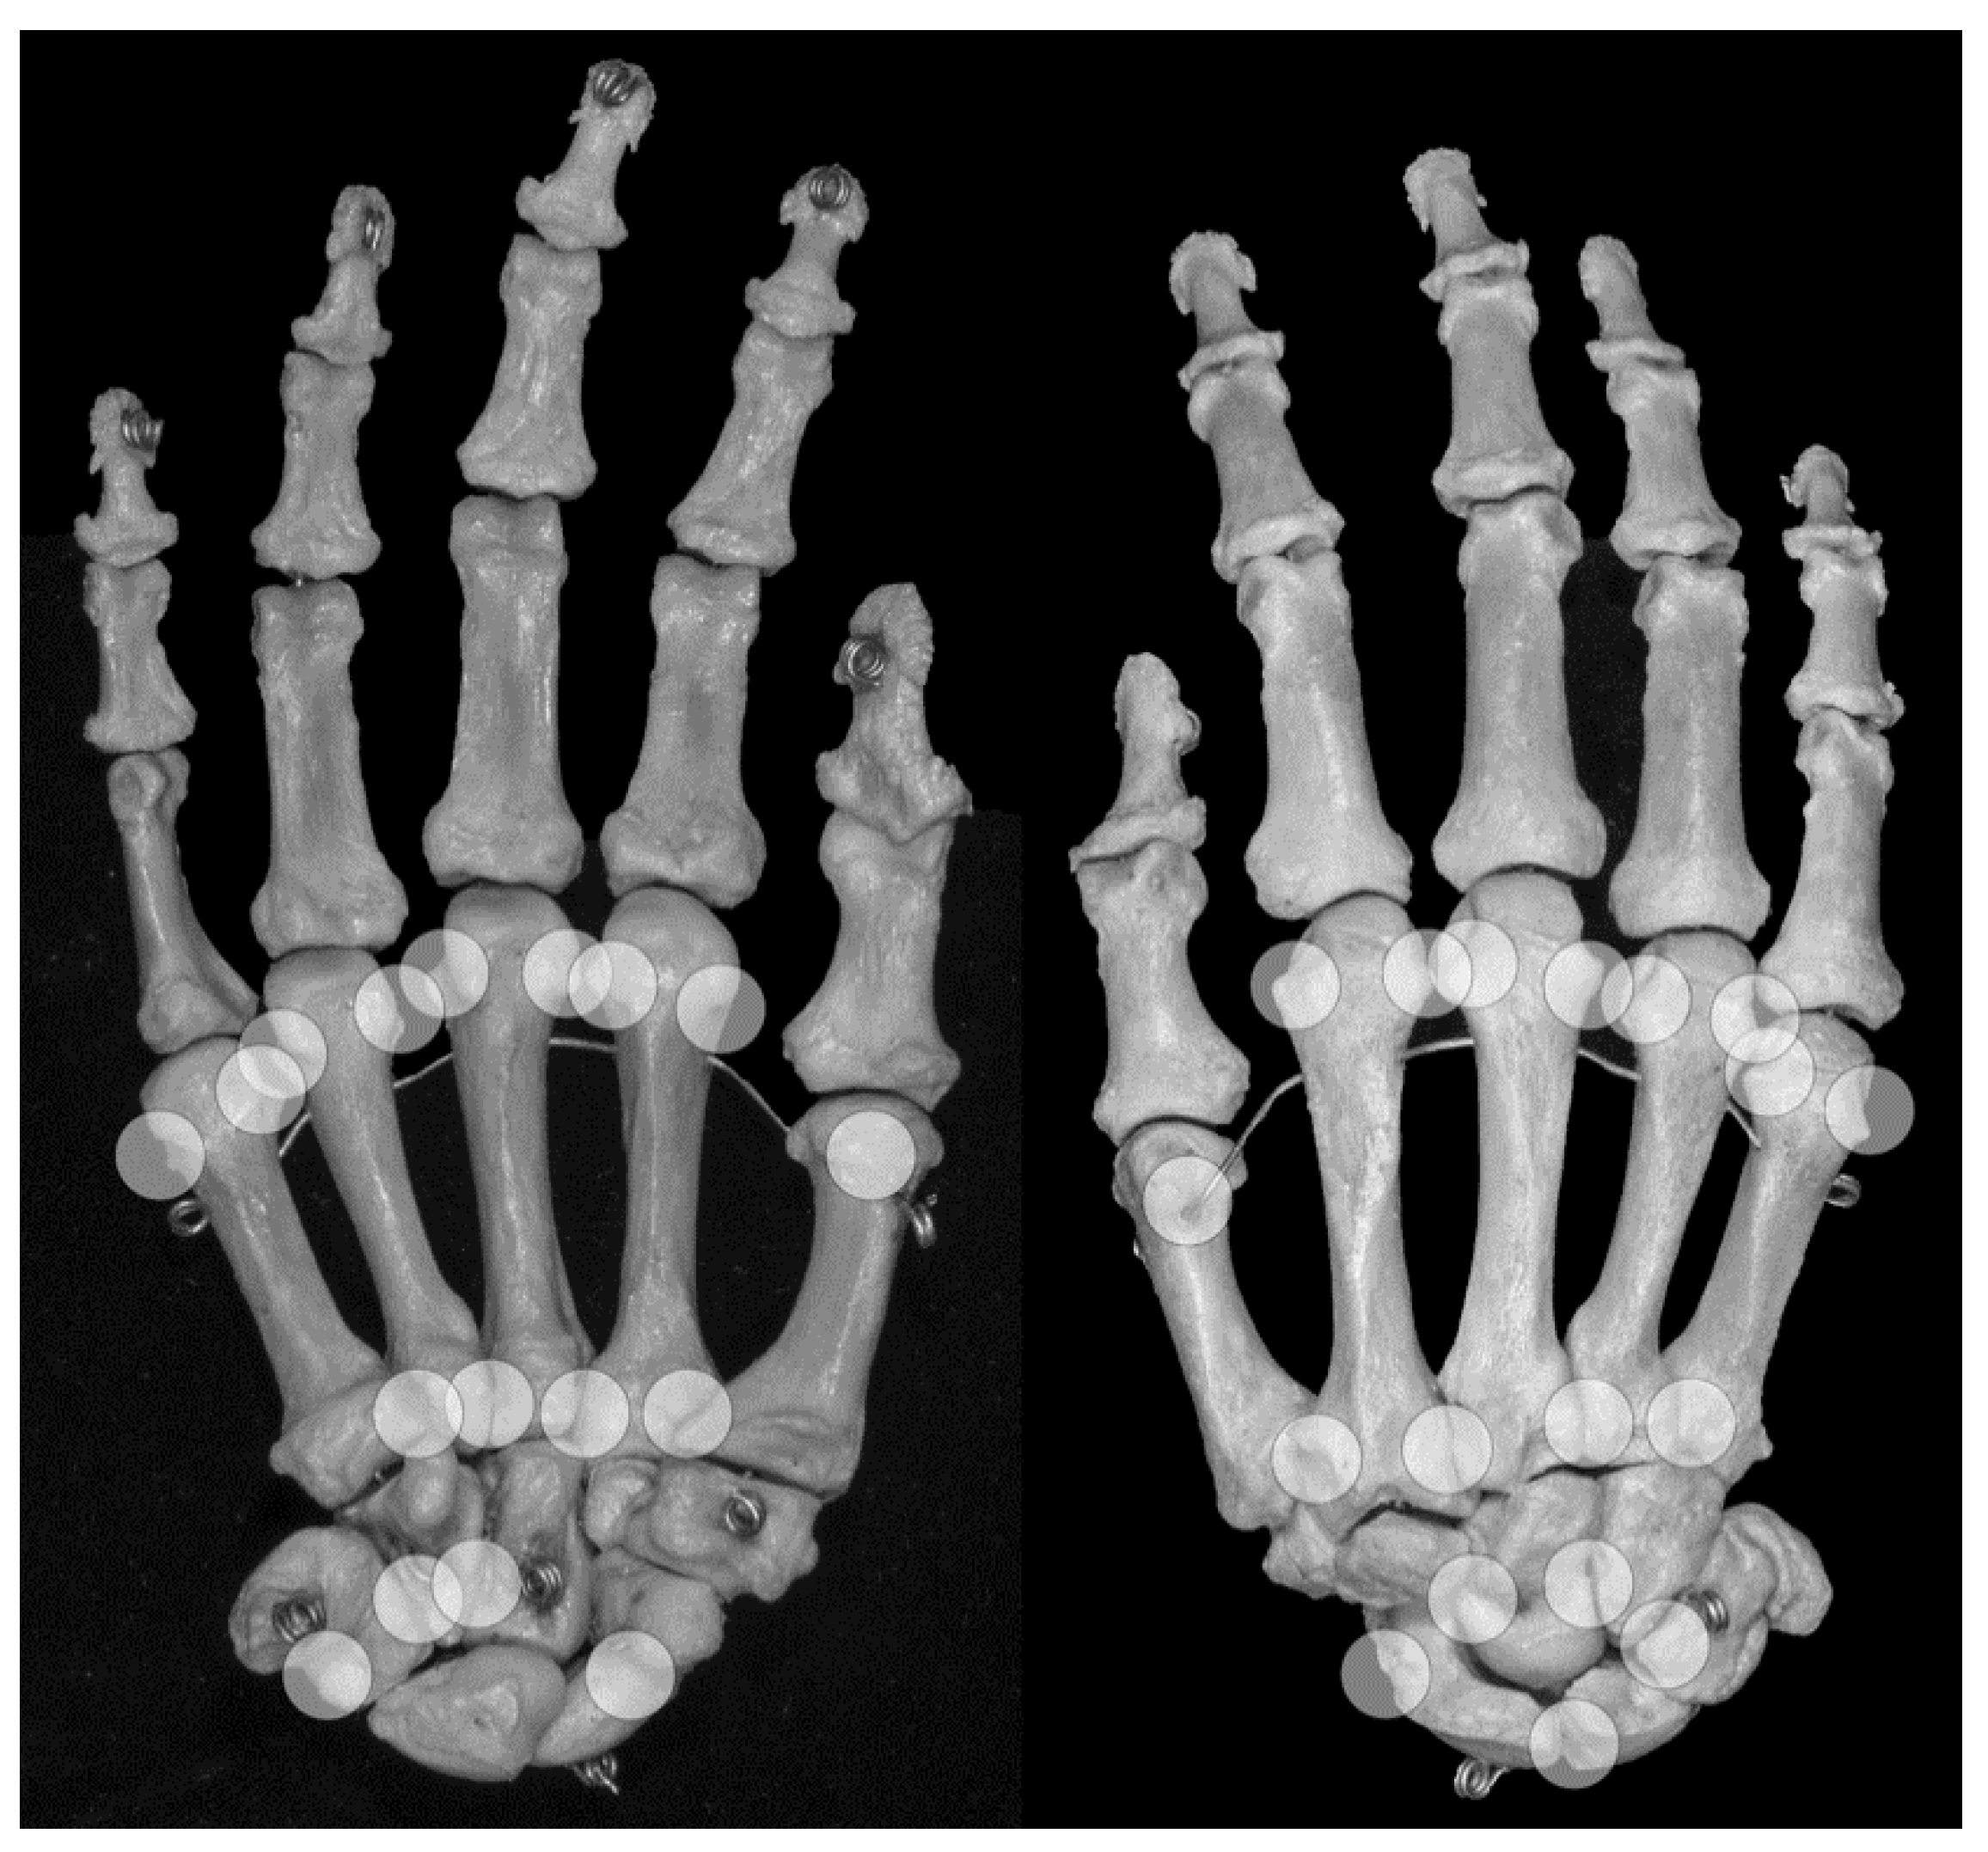

Figure 4. Locations of anatomical pseudoerosions. Overview on possible locations of anatomical pseudoerosions as summarized in Table 3. Right skeletal hand, on the left view from palmar, on the right view from dorsal.

4.1. Anatomic Pseudoerosions

An anatomic pseudoerosion can be defined as a normal concavity of a bone outlined by a smooth and thin calcified zone with the potential for a false-positive misinterpretation of an erosion. In this form, the term pseudoerosion is more precise than “notch” or “bony depression” and may be preferred as it contains a prognostic impact for the imaging assessment of arthritis. Such clinically oriented annotations, examples are the scaphoid waist and the metacarpal neck as typical sites for fractures, have been in use in traumatology and may be of help in the assessment of arthritis-related erosions, too (list of described pseudoerosions in Table 3, an overview of anatomical pseudoerosions in the hand may also be found in Figure 4).

Grooves due to ligament or tendon insertions have a varying appearance as described in the enthesis concept by Benjamin and McGonagle [79]. Such prominent grooves can cause the appearance of a pseudoerosion (Figure 2a). A groove may occur in three forms: (1) at a non-apophyseal direct tendon or ligament attachment where the uncalcified components of the enthesis enters the bone, (2) at an apophysis with overhanging edges, or (3) at an incomplete apophysis, a jutty, at the indirect attachments of a tendon or ligament with a tangential transition into the periosteum. For example, pseudoerosions resulting from the first form are the metacarpal ligament insertions at the bases of the metacarpal bones [80]. At the dorsal aspect of the triquetral bone, such a pseudoerosion may be formed by the distal insertion of the radiotriquetral ligament along with other components of the dorsal radiocarpal ligament. On the capitate, on which several strong carpal ligaments have their insertion, and many other carpal bones, intercarpal ligaments may cause pseudoerosions [51]. Examples for the second form may be the non-spherical form of metacarpal and metatarsal heads, which can be explained by the collateral ligament complexes running laterally and medially with smoothly outlined shallow metacarpal grooves containing these structures. At the metacarpals, these grooves are bordered by little tubercles for the proximal attachment of the collateral ligaments (Figure 4) [81]. Moraes do Carmo et al. [54] identified three concavities in the first metacarpal head (intersesamoid, ulnar, and radial) and two in those of the fingers (ulnar and radial). They described dorsal depressions of the metacarpal heads due to the extensor digitorum tendons in one third of their anatomic specimens which correlated with observations with ultrasound made by Boutry et al. [82,83]. A similar study was done for defining pseudoerosions of the metatarsal heads by Torshizy et al. [55] who described anatomic variations in the normal osseous concavities of the lateral and medial aspects of each metatarsal head. Typical jutties, i.e., examples for the third form of grooves, are the small round or oval subcapsular notches at the proximal phalangeal bases [80,84]. At the Achilles tendon insertion, proximal to its jutty shallow irregularities beneath the calcaneal bursa may represent true erosions [85].